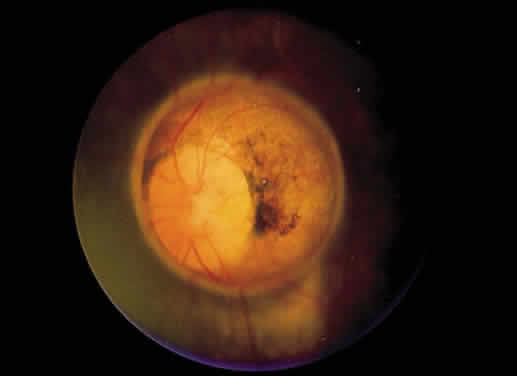

Retinochoroidal colobomas are glistening white or yellow defects with distinct borders that occur inferior or inferonasal to the optic disc (Fig. 12). They may extend up to and involve the optic disc (Fig. 13), or they may be seen as isolated chorioretinal defects. The margins of the coloboma often are pigmented, and the defect is filled with abnormal retinal tissue. Anteriorly, the defect can extend as far as the iris and produce an inferonasal gap (Fig. 14). These anomalies may occur in otherwise normal persons or in association with chromosomal abnormalities or multisystem diseases, such as trisomy 13, the Aicardi syndrome, Goldenhar's syndrome, and the CHARGE association.148,152,153 Occasionally, autosomal dominant or recessive inheritance patterns are found, but often none are evident.152 In families with autosomal dominant inheritance, variable expression of the genetic trait makes genetic counseling difficult.154

Fig. 12. Isolated retinochoroidal coloboma with pigmented borders positioned inferior to the nerve head. The sclera is visible through the thinned, overlying retinal tissue.

Embryologically, retinochoroidal colobomas arise from failure of the embryonic fissure to close. Consequently, the inner and outer layers of the optic cup are abnormal in this region. The inner layer (sensory retina) usually is present as a membrane of undifferentiated retina that may have blood vessels going through it (see Figs. 12 and 13). The outer layer (RPE) is absent, and since the choroid is dependent on the RPE for its development, it also is lacking.